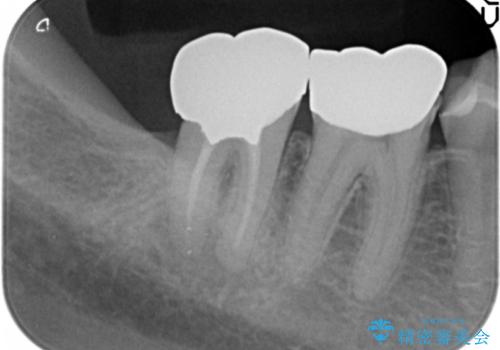

- 上顎臼歯部の欠損にブリッジ治療、目立つ下顎奥歯の銀歯をセラミックへの置き換えを希望され来院されました。

審美性と耐久性に優れるフルジルコニアクラウンでの治療を計画します。

- 49.5万円 (フルジルコニアクラウン×5)費用は治療当時の料金となります